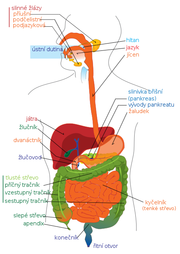

| 17. 5. 2011, 19:08 | Digestivni system diagram.png (soubor) |  | 104 kB | Webmaster | 2 | |